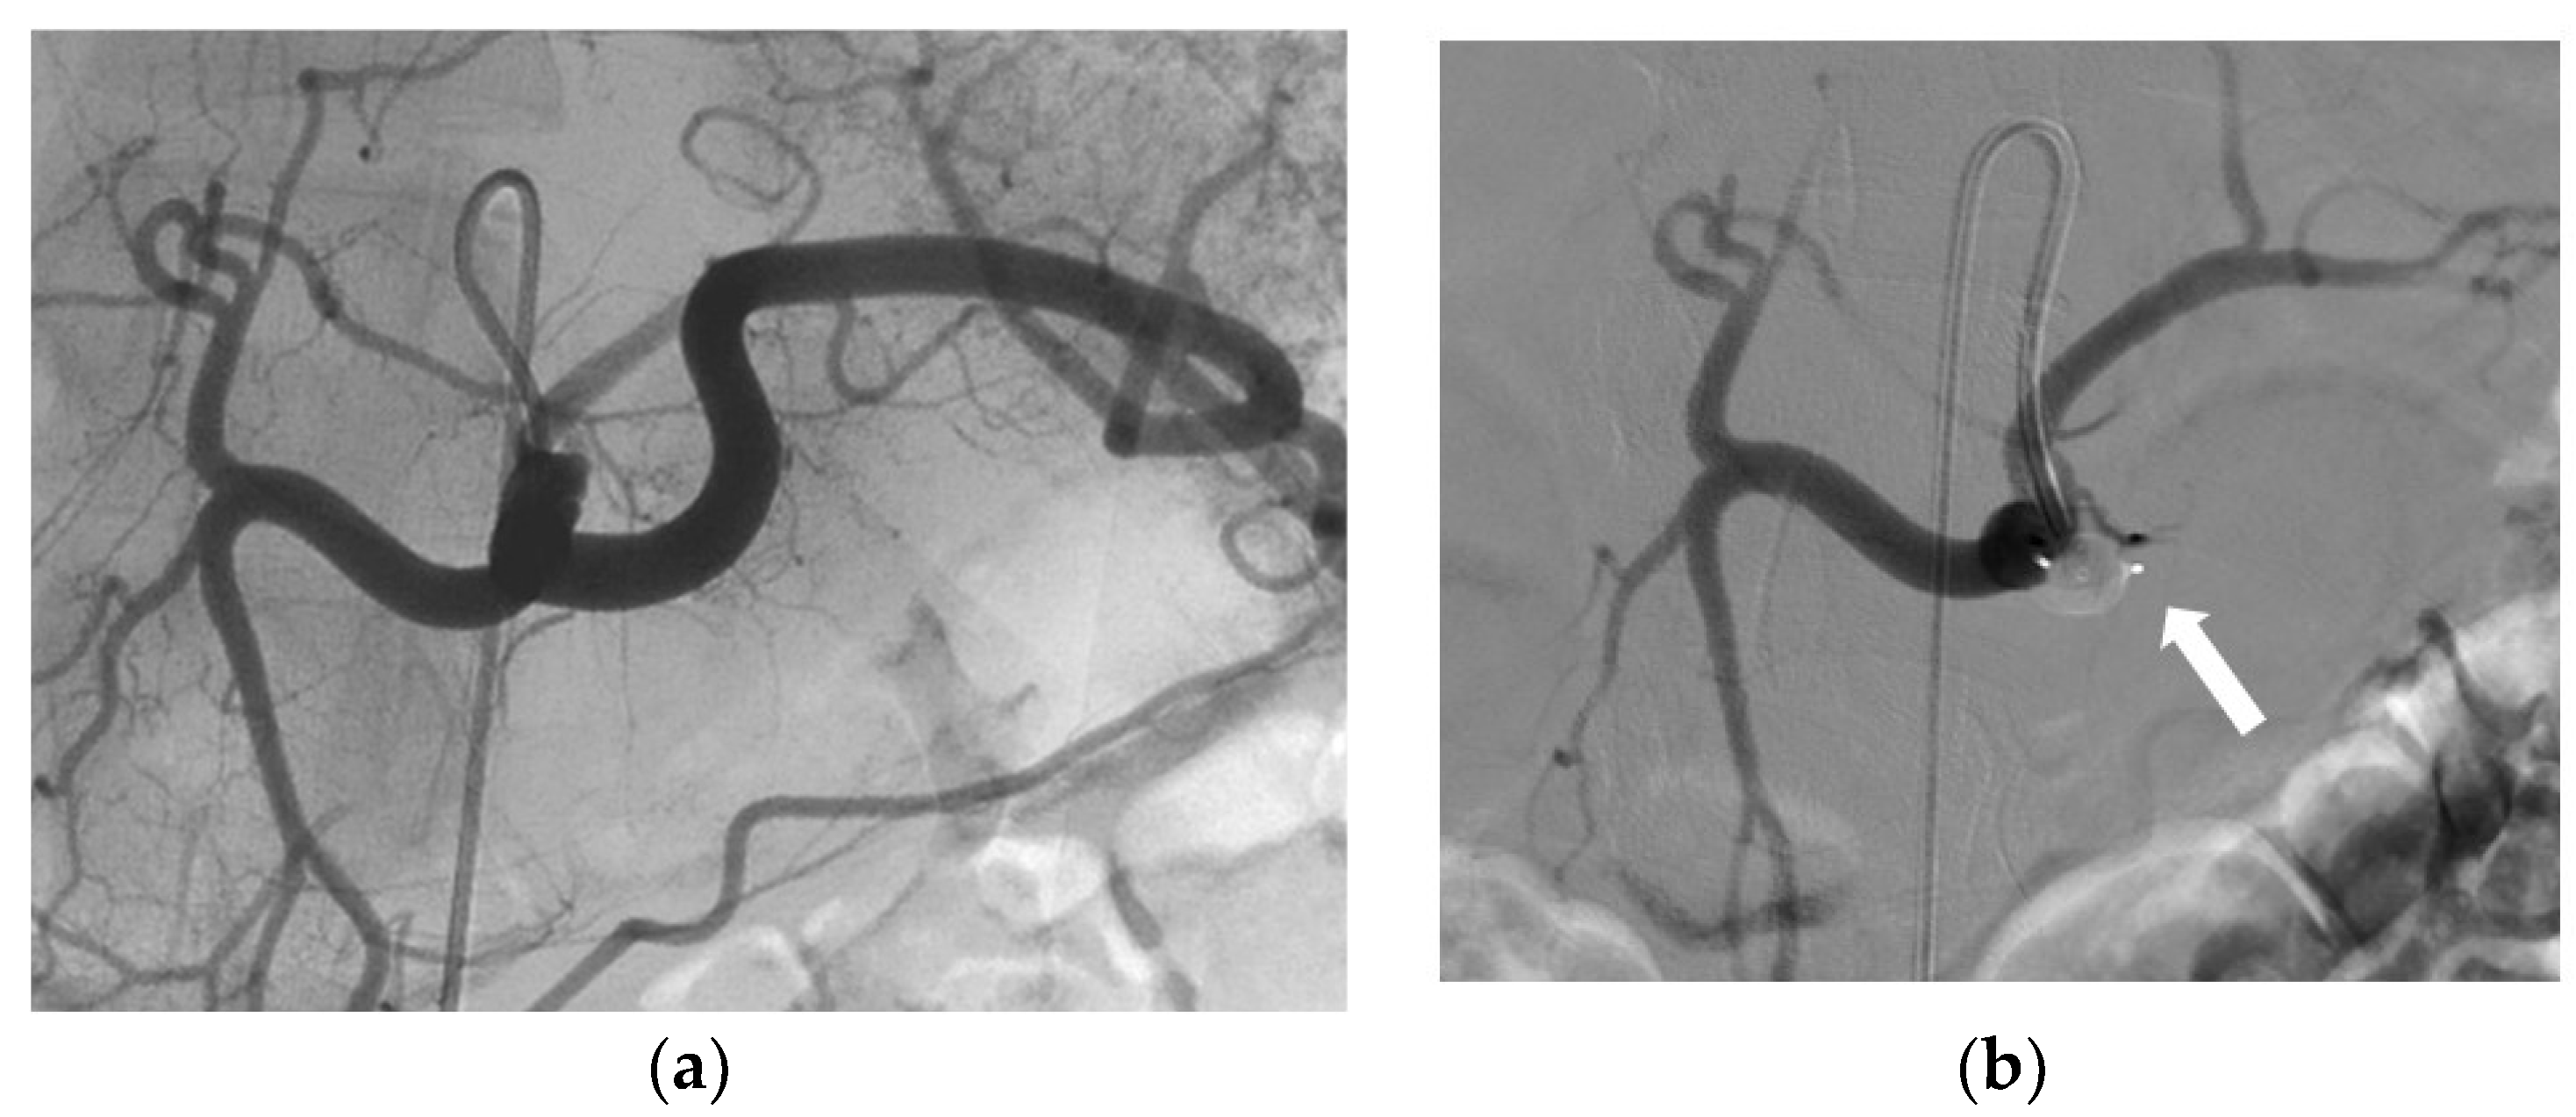

| Arterial aneurysm | 8 (7.2) |

| Occlusion/recalibration TIPS 1 | 7(6.3) |